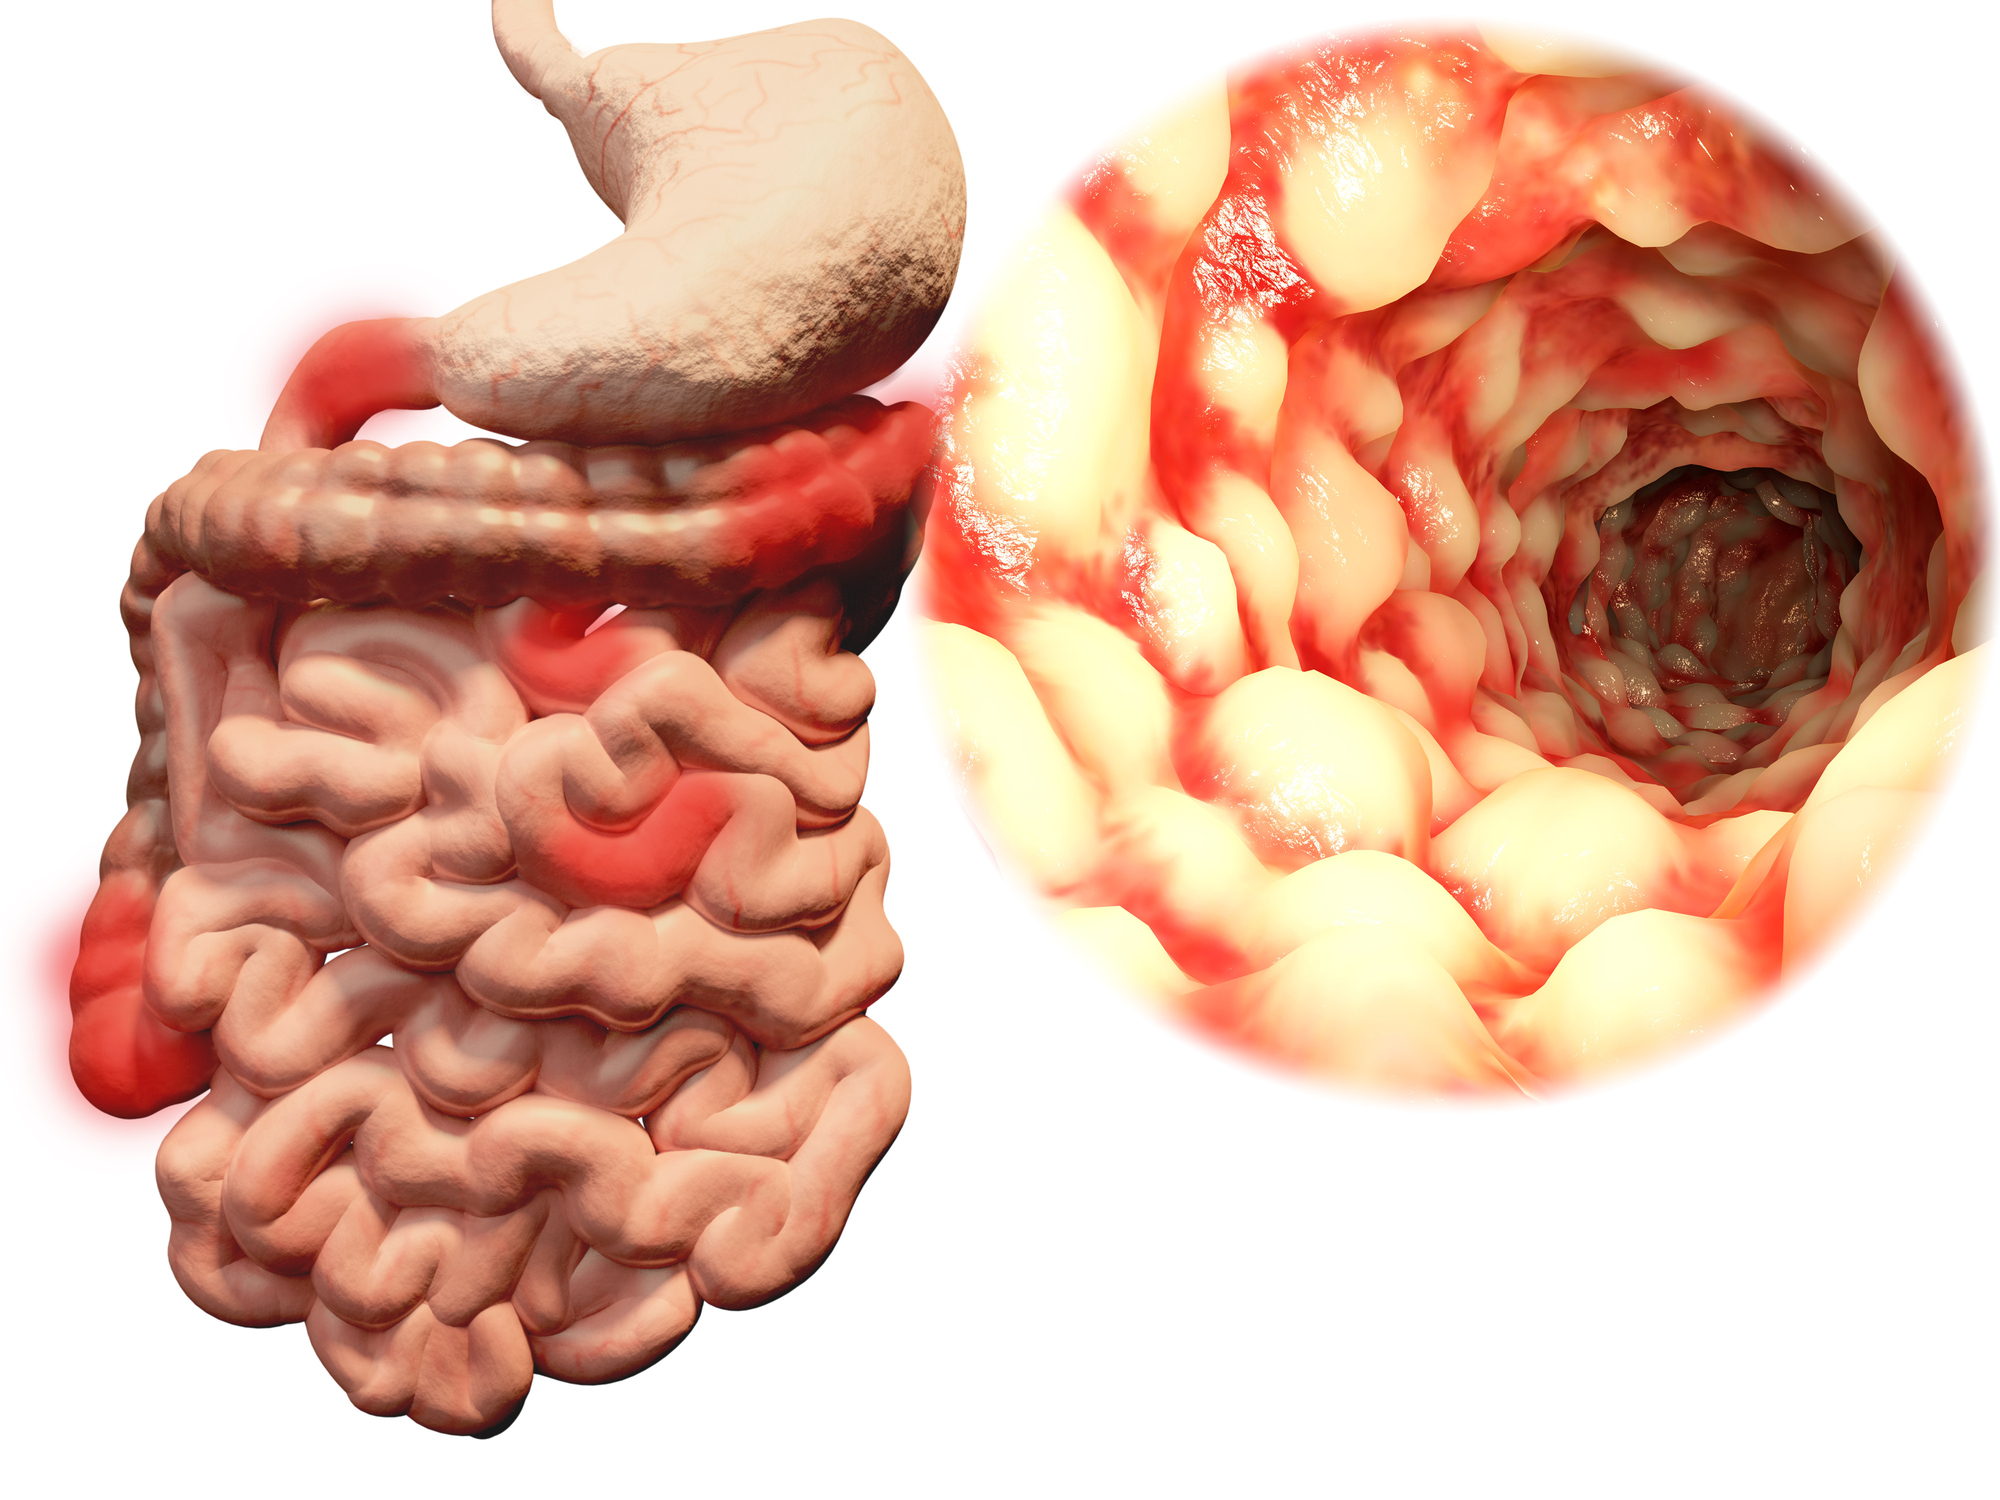

This week’s health news roundup includes recent stories about celiac disease, ulcerative colitis, rheumatoid arthritis, fibromyalgia, and inflammatory bowel disease (IBD). This week, we discussed the benefits of going gluten-free in celiac disease, possible treatment for ulcerative colitis, risk of cancer in rheumatoid arthritis, positive impact of aquatic aerobics on fibromyalgia patients, and the problem ...click here to read more